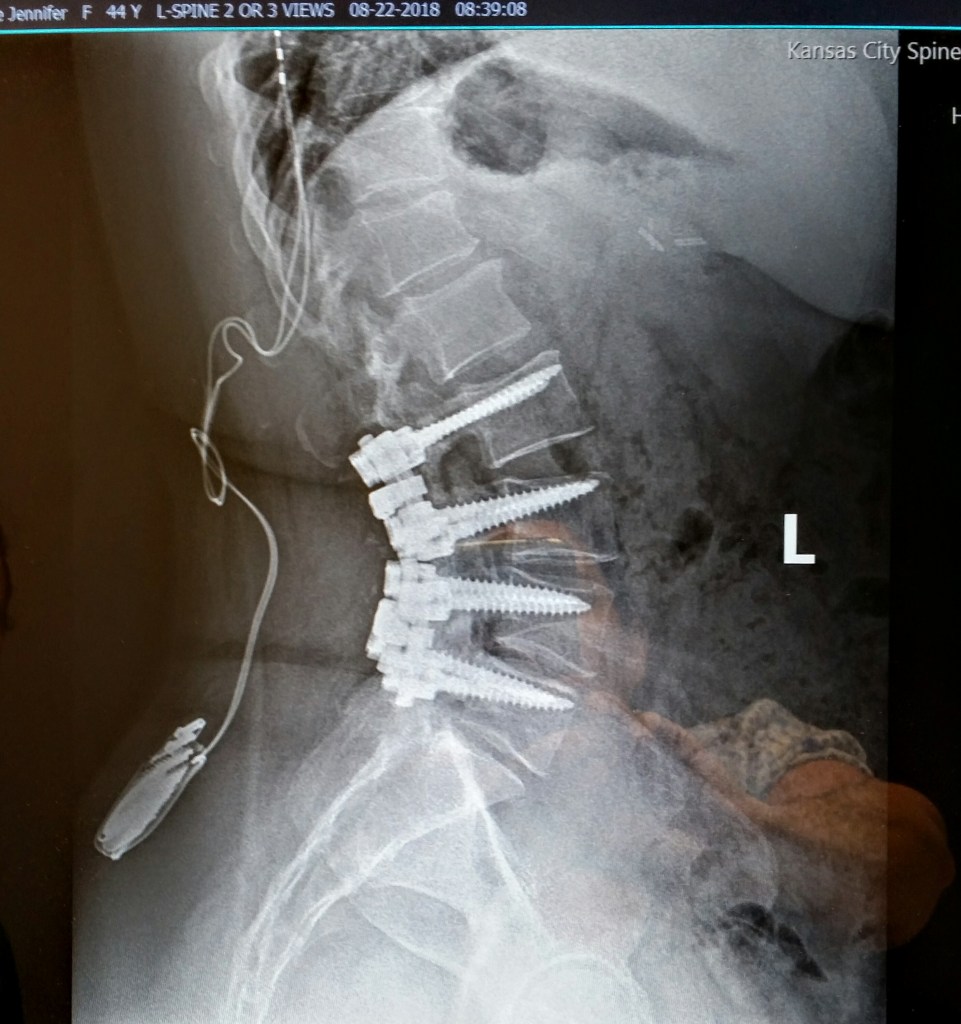

The diagnosis: There are bone spurs growing (spinal stenosis) from my neck to tail, as well as degenerative disc disease. Two thoracic discs are herniated, three of four discs in my neck are broken, I have lumbar osteoarthritis, kyphoscoliosis (which means the spine curves incorrectly from side to side, but also front to back), my neck curves the wrong direction (reverse cervical lordosis), I have a spinal stimulator, and I’m fused from L2/L3/L4/L5 and next month I can add L5/S1. The levels that really need the surgery are at the top of the fusion (T11/T12/L1), but they are dangerous to do as it is lung and cord level, plus the bone may crumble (I have osteoporosis as well). But the discs have degenerated so much in the last year that both of those top levels are pressing against the thecal sac (which is the sleeve that holds your spinal cord). I will likely need that surgery soon. Probably next year. Then I will be fused from the bottom up to T10. That doesn’t make me happy.

[Update 6/6/20: The Surgery went well. The disc between L5 and S1 was completely crushed and being forced out the side. So the surgeon said he fashioned a cage in that fusion (It’s the little cylinder below that looks like a bullet). I’ve only ever had Steri-strips to close the wound, but this time they used staples–25 staples–and I’ll having them removed was fun. Of course, the first thing I did was pull out half of the bottom staple, but the others held. They itch like crazy. I’m trying to work, but I’m only up for about four hours at a time, then sleep for three–between medication doses. I got a fabulous anesthesiologist this time who’d just had training on chronic pain patients and knew to give me extra medication, and I did beautifully. I’m taking lots of walks around the block with my walker, like a granny. Lol. The opiates make me very emotional, as well. I will take them as a normal patient would, then go back to my Subutex doctor. If I didn’t need him, I’d leave though, because his behavior throughout this ordeal has been unfathomable to me, and uncaring at best. Thank you for all your support! I’ll keep you updated.]